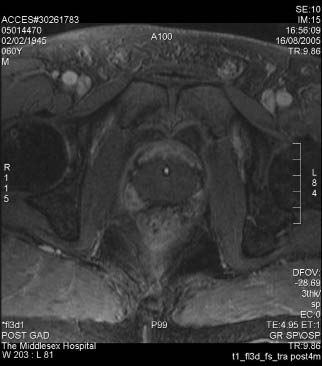

9) Retained “slough” that is preventing adequate bladder emptying can usually be resected or scraped out with a cold loop. The ultimate goal is that, after the sloughing of the ablated tissue, there will be a significant prostate defect as shown in the MRI images before and after HIFU treatment, Figure 5.

Figure 5. Pre-HIFU and Post-HIFU MRI images of the prostate.

MRI image of prostate before HIFU

Post-HIFU MRI showing cavity after prostate ablation and sloughing.